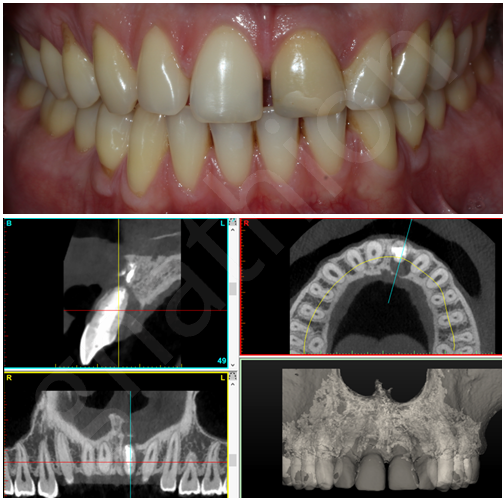

Παρουσιάζουμε μια τέτοια σχετικά απλή περίπτωση για να γίνουν κατανοητά τα ενδεχόμενα στάδια και ο χρόνος της αποκατάστασης . Αφορά νεαρό άνδρα που παρά τις επανειλημμένες προσπάθειες ενδοδοντικής θεραπείας για να διατηρηθεί ο άνω αριστερός κεντρικός τομέας (#21) η φλεγμονή στο σστό επεκτεινόταν.

Η επέκταση της βλάβης, όπως αυτή επιβεβαιώθηκε με υπολογιστική τομογραφία(CBCT), αφορούσε το χειλικό και το υπερώιο οστό (Εικόνα 1). Στο πρώτο στάδιο θα γινόταν εξαγωγή του δοντιού, καθαρισμός του οστού και τοποθέτηση μοσχευμάτων για την ανάπλαση της περιοχής που θα υποδεχόταν αργότερα το οδοντικό εμφύτευμα.